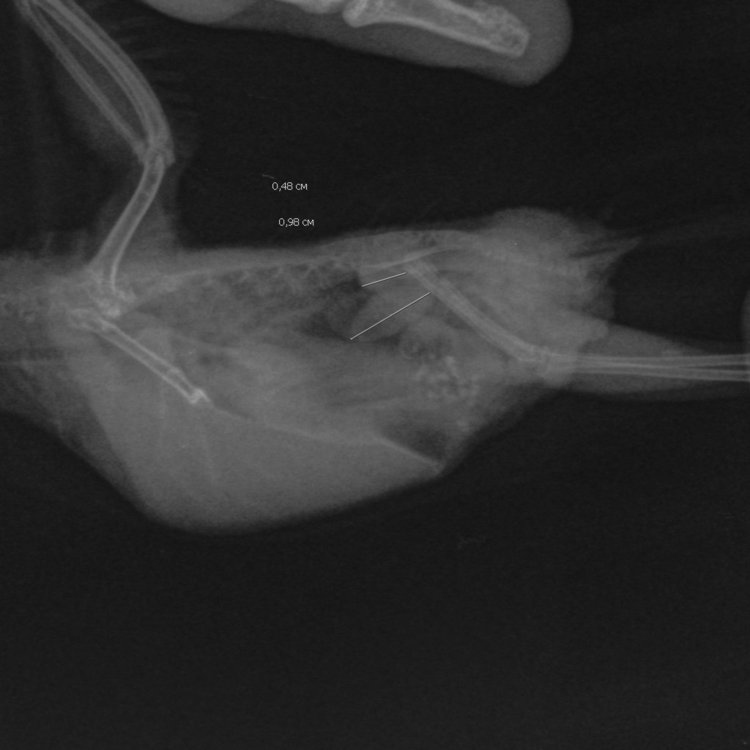

Опухоль семенников у волнистого попугая

был сделан рентген и клинич. анализ помета

15974870568708932973678521616638.thumb.jpg.9209403987994d515592bac03c5c37b3.jpg1020074747__-.-15_08.2020-9_48_06-704.thumb.JPEG.57b7af1b597a65a1158fc6ae91579ba0.JPEG

P. S. Рентген без даты и времени почему то, так что не уверена на 100% что наш((...

Рентген у вас более чем адекватный,даже с выставленными линейными размерами семенников.

Анализ есть, по которому есть воспалительный процесс (что мб. связано с семенниками).

Если увеличение семенников связано в гормональным взрывом- терапия имеется, и наверняка вам ее назначили.

Если  с н/о- так же есть, с различными вариантами исхода, и ваш доктор наверняка это тоже знает.

По вашим назначениям- доктор предполагает восалительный процесс семенников , и как следствие- возможные проблемы с ЖКТ. Назначения даны исходя из этого.